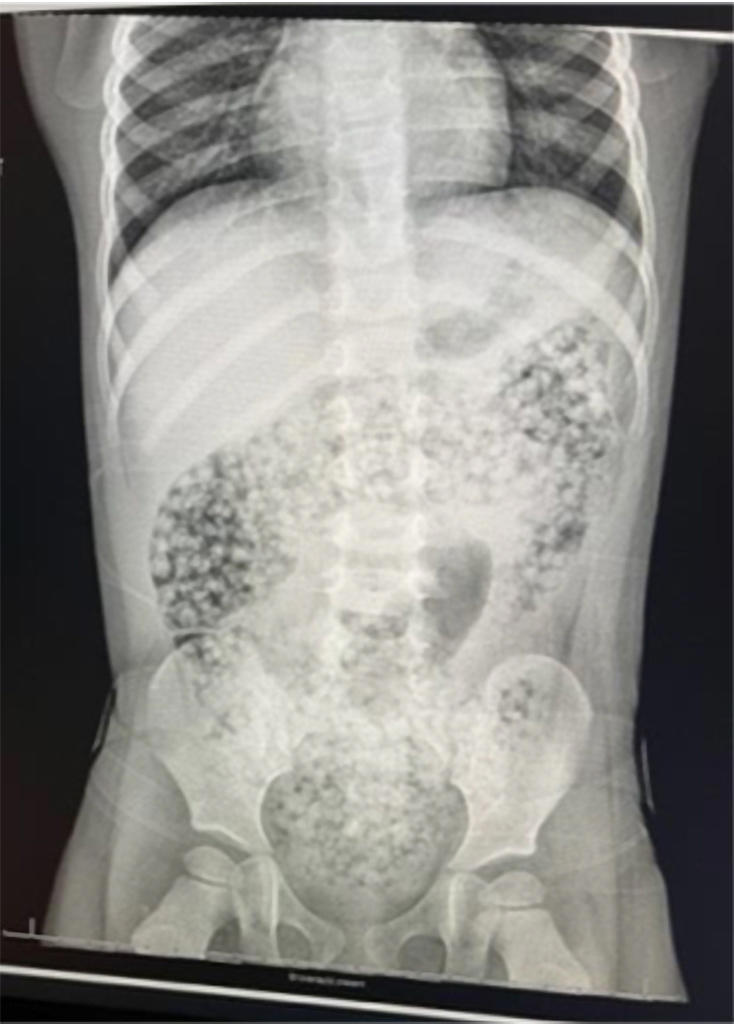

Waterabsorbing bead ingestion. a Abdominal radiographs indicating... Download Scientific Diagram

Waterabsorbing bead ingestion. a Abdominal radiographs indicating... Download Scientific Diagram Water Beads Ingested  Kids also have put the beads in their ears and even inhaled them. The sensory toy poses a choking hazard and can cause intestinal blockages if accidentally swallowed. The beads kipley ingested contained acrylamide. The problem is that because water beads look like candy, young children may be tempted to swallow them. About five years later, haugen created that water. Water Beads Ingested.

Figure 1 from Small bowel obstruction by water beads in a 12monthold girl presenting with Water Beads Ingested  And can lead to choking, internal. The research conducted by the center for injury research and policy and central ohio poison center showed there were more. The beads kipley ingested contained acrylamide. The sensory toy poses a choking hazard and can cause intestinal blockages if accidentally swallowed. About five years later, haugen created that water bead lady, a. The problem. Water Beads Ingested.